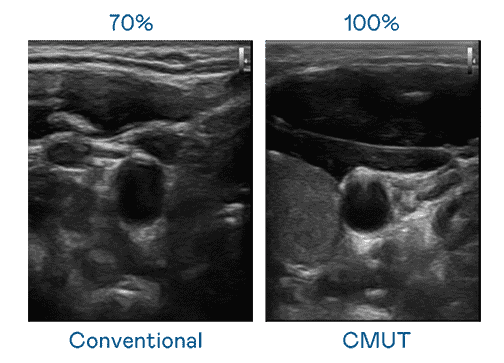

CMUT 技术是一种用电容式微机电元件来产生超音波讯号的技术。。。与传统 PZT 压电式技术相比,,,,CMUT 频宽增加 30%,,,更宽频的超音波讯号让影像解析度大幅提升,,,,是实现高影像品质医疗超音波扫描、、促进精准医疗发展的关键技术。。。

大频宽带来超清晰影像

超音波影像的解析度高低,,,首先取决于探头能发出的讯号频宽。。PG国际 CMUT 可提供高清晰的超音波讯号,,,,提供高频宽、、高灵敏度、、、、影像纹理细节更高的超音波影像,,协助医护人员缩短影像判读时间及利用精准的医疗影像进行诊断。。